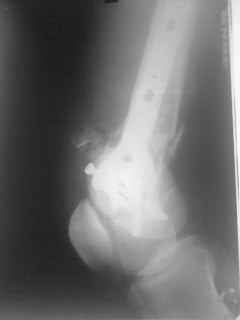

01.12.09г. оперировал больного с подобной травмой в ЦРБ на 4-е сутки после ДТП. Перелом открытый - рана находилась медиально чуть выше надколенника длиной примерно 3-4 см. До этого при поступлении было выполнено ПХО раны и скелетное вытяжение. На момент операции рана без признаков воспаления, состояние больного удовлетворительное.На первичных снимках перелом А3. На операции оказалось С3. Перелом фиксирован мыщелковой пластиной. Для репозиции понадобился медиальный доступ. Медиальный блок дополнен костно-губчатым аутотрансплантатом. На сегодняшний день раны заживают первично, швы еще не сняты, температура тела нормальная, отек бедра значительно уменьшился, имеется анемия средней степени, проводится ЛФК. Фото досылаю

Чем остеосинтез аппаратом в этом конкретном случае был бы предпочтительнее - и менее инвазивно, и пластику бы не надо было делать, и ось можно было бы лучше контролировать, включая послеоперационный период. А сейчас варусный коллапс градусов 15, и для исправления оси потребуется отдельная операция...

Снимки лучше бы делать на большем протяжении.